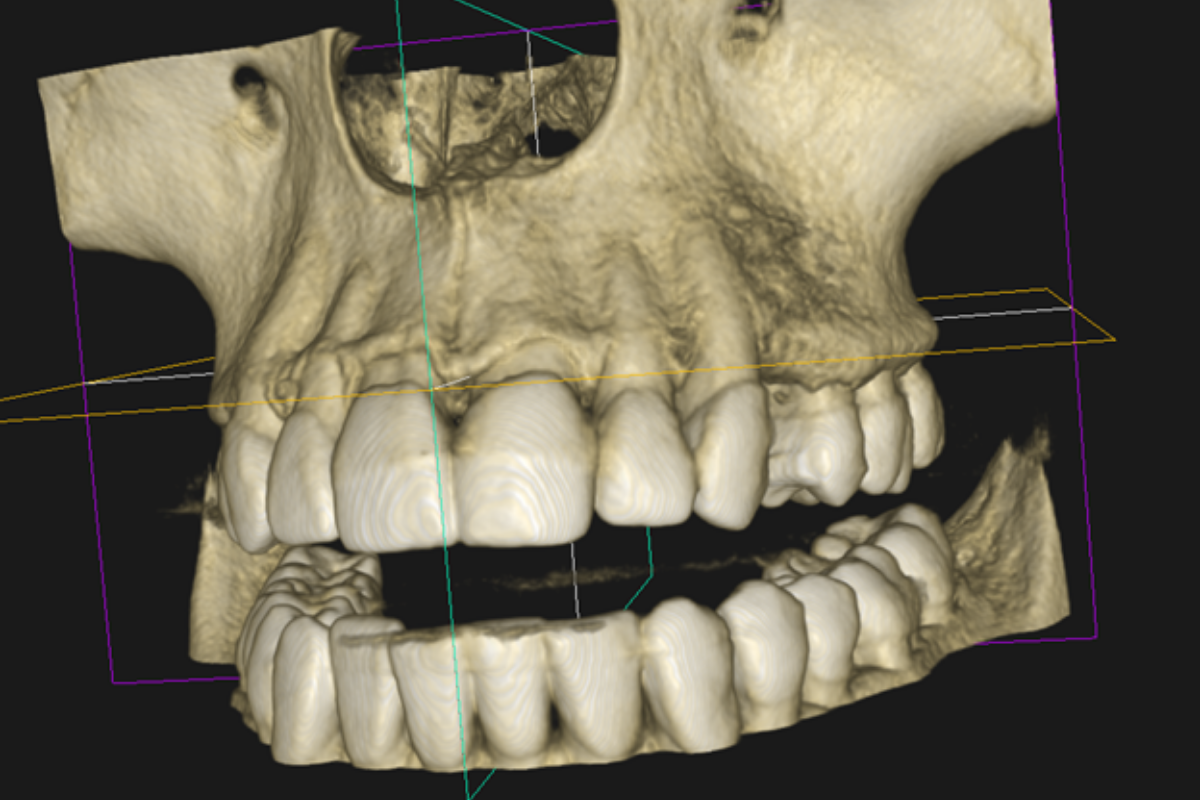

- Implantes: relación con estructuras anatómicas, evaluación ósea y planificación.

- Cirugía: planificación anatómica, terceros molares, evaluación de riesgo.

- Ortodoncia/ortognática: soporte 3D y planificación digital.

- Visualización y navegación por cortes (en CBCT) para análisis clínico.

- En CBCT, indicar región y objetivo para ajustar FOV y resolución.

¿Cómo recomiendan solicitar un CBCT para implantes?

Indica zona y objetivo clínico (p. ej., “implante 36”), y si requieres énfasis en estructuras anatómicas específicas. Con eso ajustamos FOV y resolución.